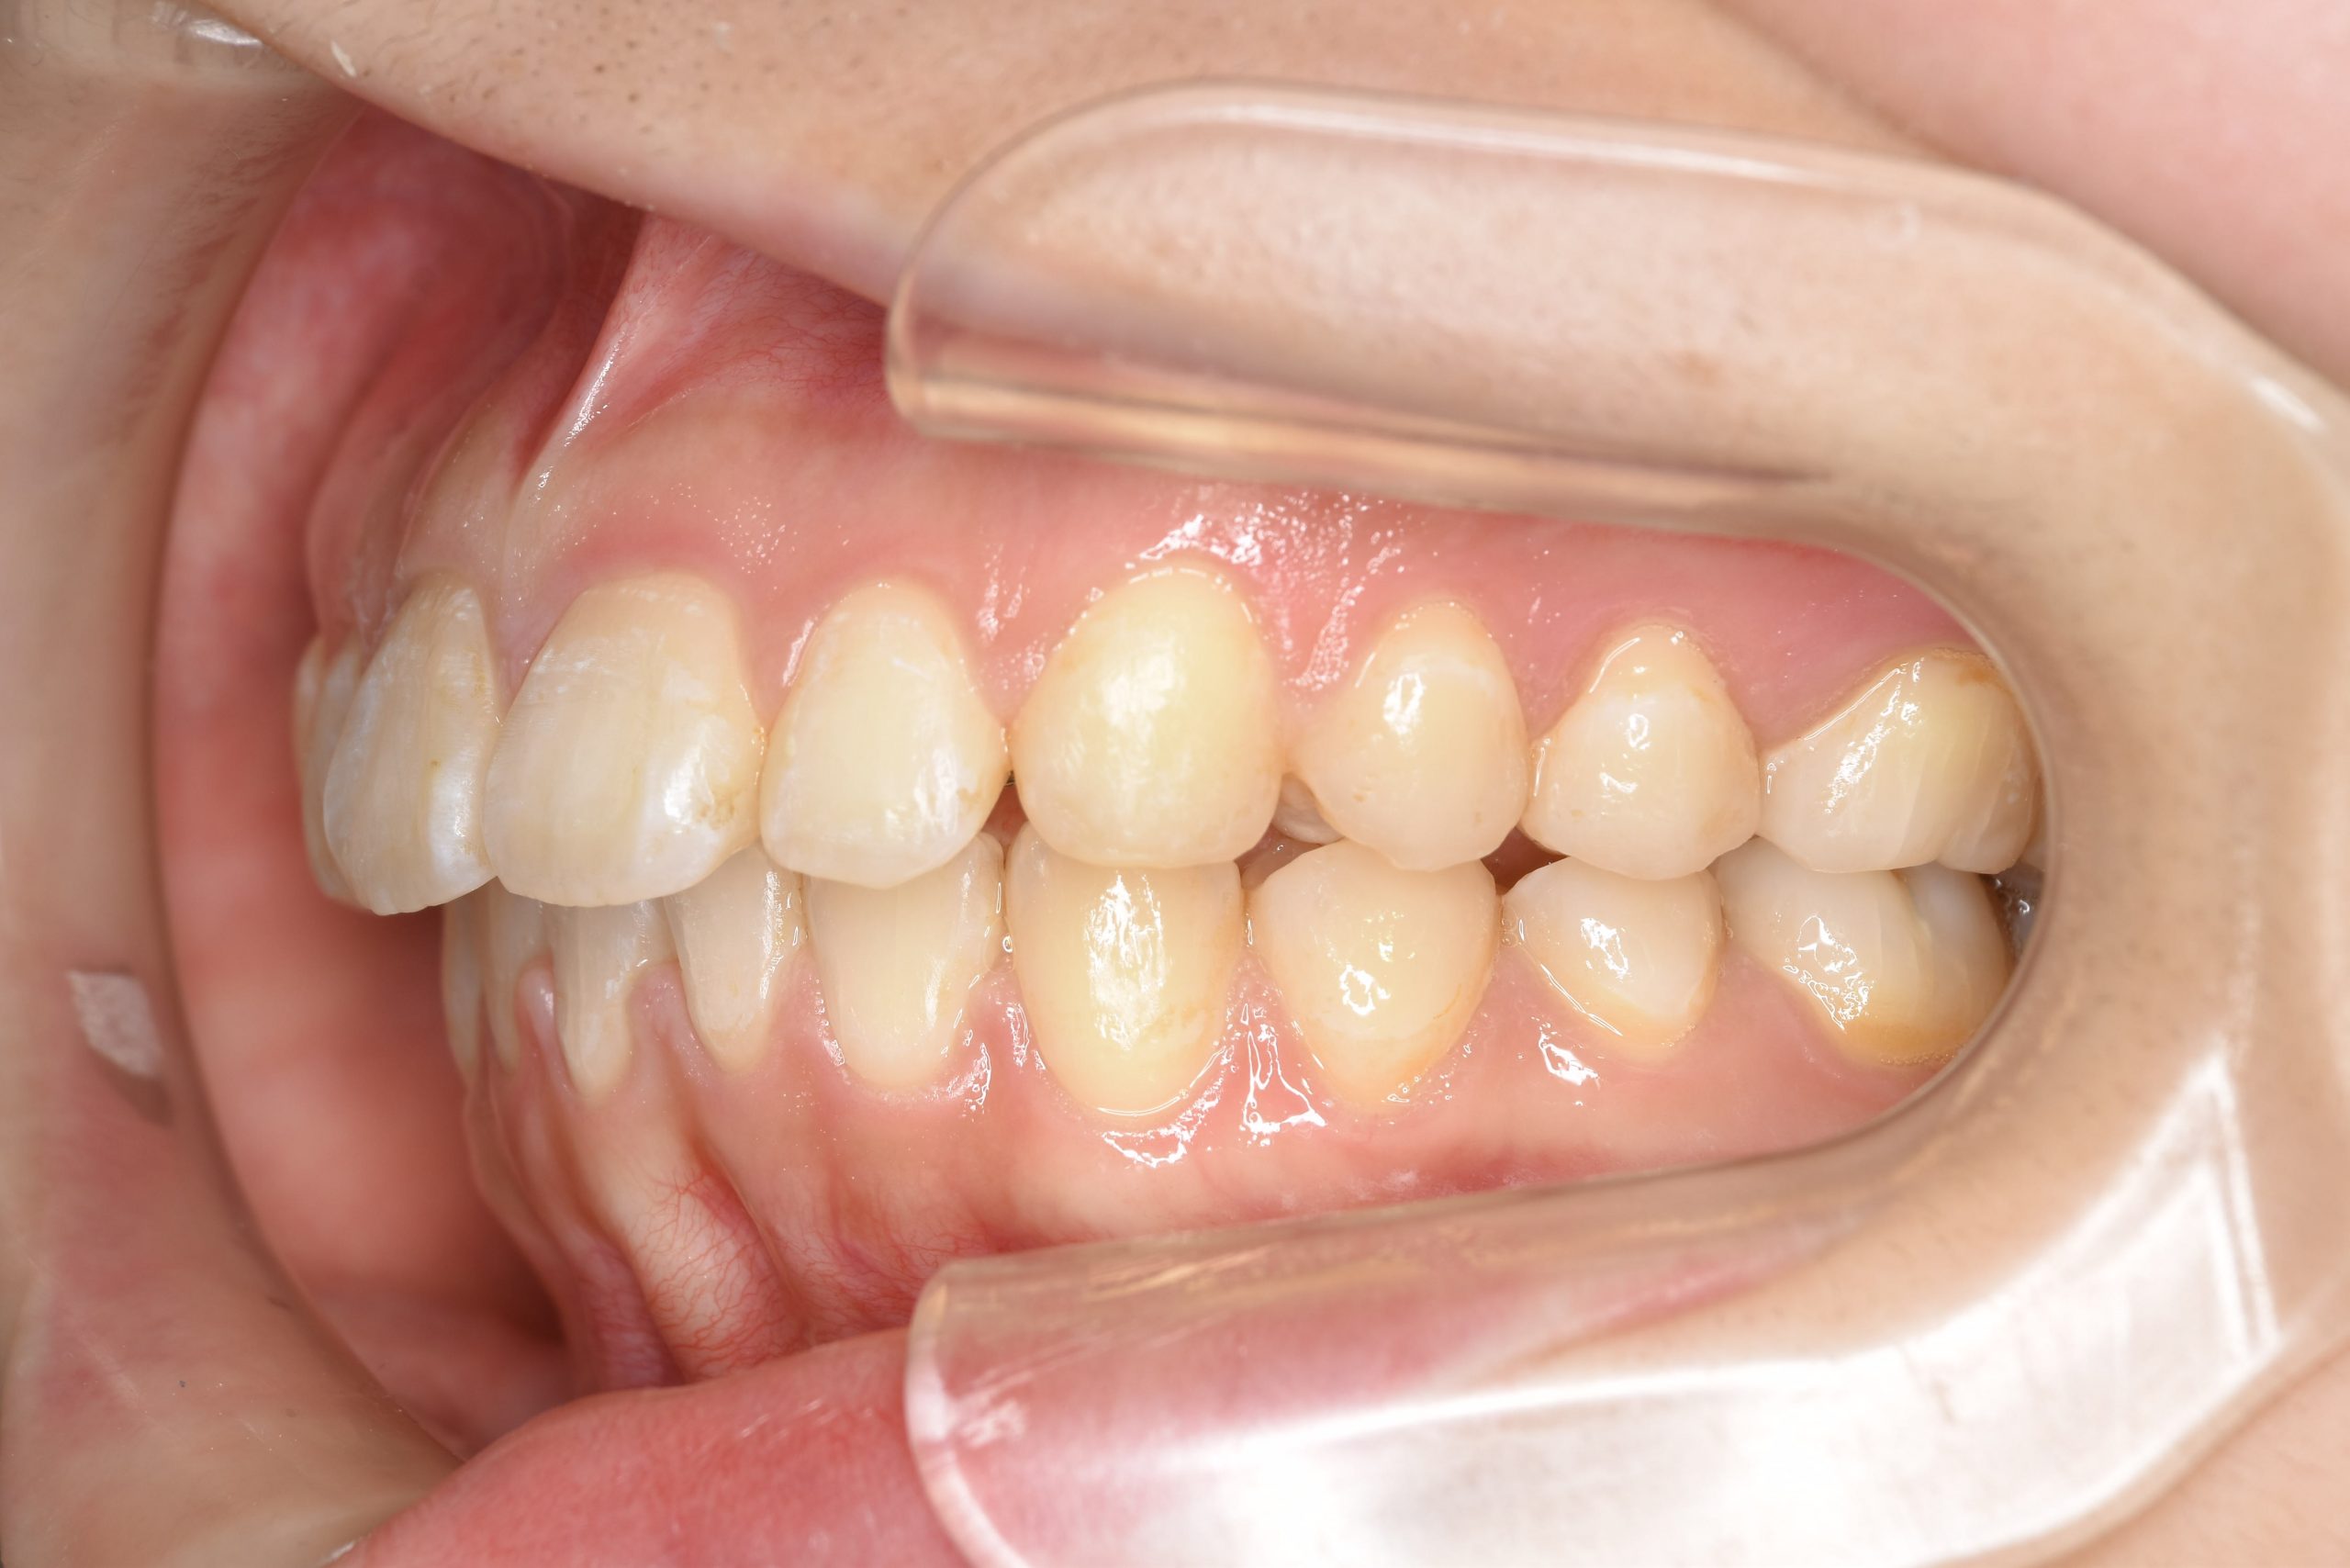

アフター

ワイヤー矯正治療|症例_349

施術内容 MSEと下顎リンガルアーチを用いて上下顎骨を拡大した。

その後マルチブラケット装置を用いて非抜歯で歯牙を配列し、良好な咬合を獲得した。

治癒期間 3年7か月間